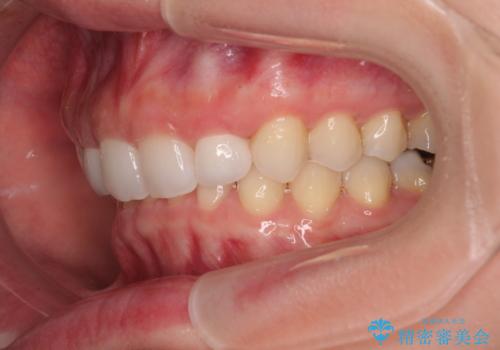

前歯のデコボコと小さい歯を改善 インビザラインとオールセラミッククラウン

- 前歯のデコボコと左右の矮小歯を気にして来院された患者様です。

矮小歯の前後にスペースを作るようにインビザライン矯正治療を計画し、矯正治療後にオールセラミッククラウンによる補綴治療を行うこととしました。

アンカースクリューを用いて上顎歯列全体を後方移動させ、極力過蓋咬合も改善されるよう計画しました。

インビザラインは長時間装着を自己管理する必要がありますが、残念ながら十分な時間の装着を行うことができませんでした。

何とか矮小歯を改善するスペースを作ることはできましたが、過蓋咬合を改善するには至りませんでした。